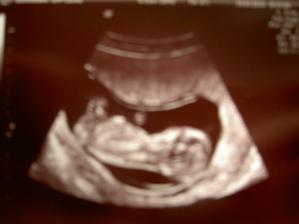

V decembri sme sa rozhodli vysadit antikoncepciu s tym, ze ak sa podari, tak sa stane... koncom decembra prisla menstruacia podla planu, ale ta januarova uz nedorazila.. ostali sme prekvapeni, ze sa podarilo tak skoro, kedze mame este len pred svadbou.. ale bez ohladu na to sme velmi stastni a tesime sa... 🙂